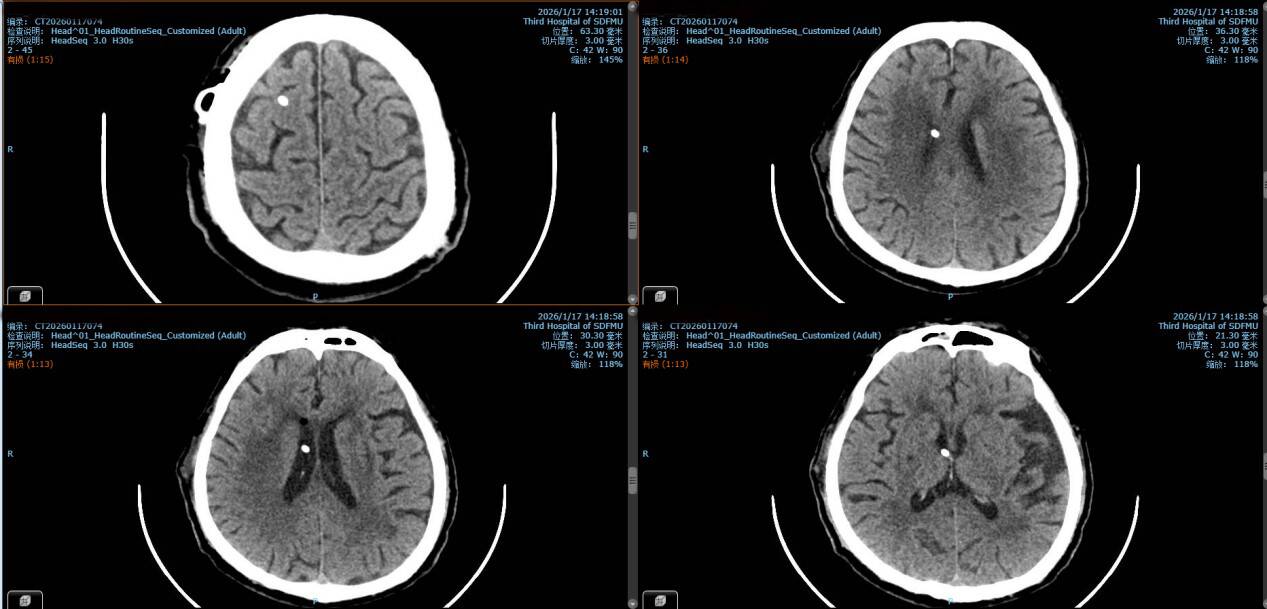

经过科内反复讨论及推演优化手术预案,与手术室、麻醉科、CT室医护人员熟练配合,1月17日手术正式实施,医疗团队按计划有条不紊地进行一系列准备工作。随后,消毒、切皮、定位操作精准推进,半小时后,副主任医师刘伟作为主刀医师,手持穿刺针一次穿刺到位,透明的脑脊液缓缓流出,标志着穿刺成功,后续顺利连接固定Ommaya囊。整个手术仅用时1小时,且为局麻操作,术后复查CT显示置管位置精准,与术前设计的靶点分毫不差。经过两天的术后恢复,患者已顺利转回呼吸与危重症医学科继续后续治疗,Ommaya囊也正式启用,为延长老人生存时间筑牢了“生命线”。